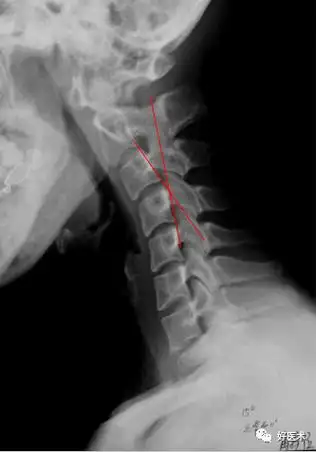

这是一个14岁湖北女孩莉莉的颈椎片子,我们看到她的颈椎几乎是一根直